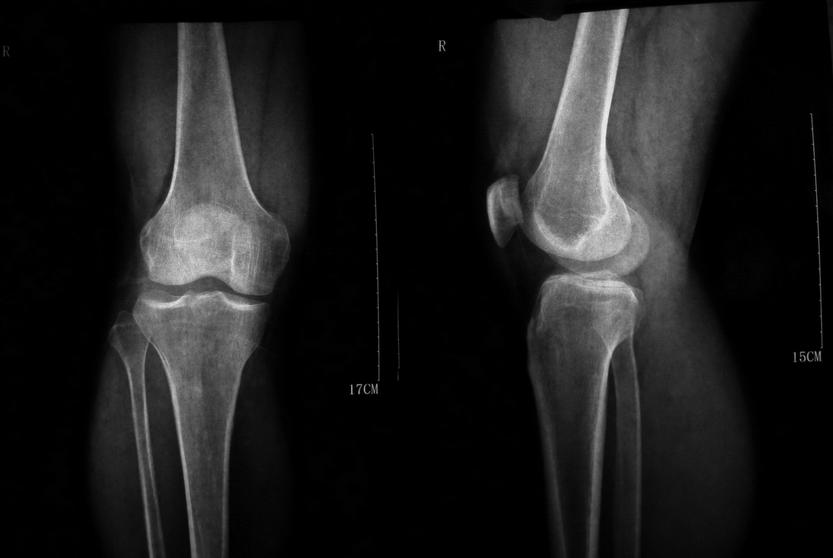

来自濮阳市范县的陈先生是一名普通农民,来到本院(郑州痛风风湿病医院)之后,自述五年前出现腰背、膝盖酸痛症状,起初以为是劳作过多太累导致的,并没有放在心上,只是买了几片膏药贴上。去年6月出现症状...[详细]